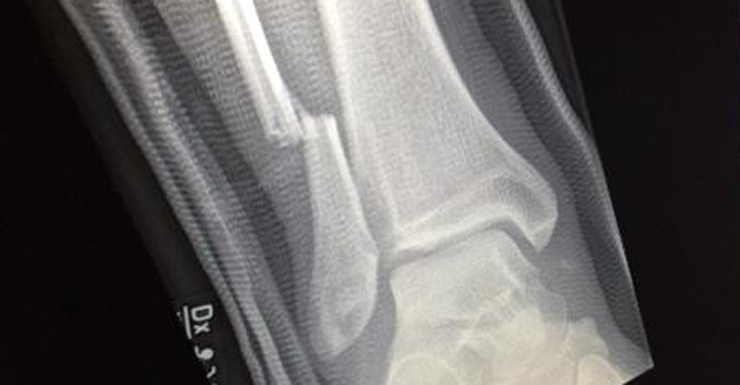

The Foo Fighters later tweeted an X-ray showing Grohl’s broken leg, saying: “Thank you Gothenburg. That was amazing.”